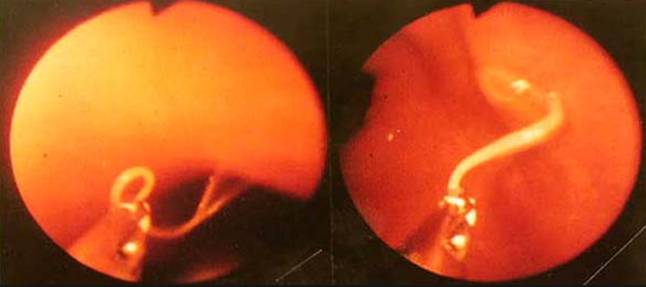

Việc chẩn đoán có thể thiết lập bằng nội soi dạ dày phát hiện ấu trùng dài 2cm, có thể lấy bỏ ra ngoài, hoặc có thể phân tích và xét nghiệm về mặt mô học thông qua sinh thiết hoặc trong quá trình phẩu thuật. Con người nghĩ rằng nguy cơ sẽ cao hơn nếu chúng ta ăn cá hoang dại hơn hơn l à các nuôi khi nhiễm Anisakiasis. Nhiều quốc gia yêu cầu các loại cá có nguy cơ tiềm tàng mà dự định ăn sống nên để đông lạnh trước đó để giết sạch ký sinh trùng.

Ngay cả khi nấu xong, Anisakis vẫn có nguy cơ sức khỏe đối với con người. Anisakids (và các loài liên quan như hải cẩu, Pseudoterranova spp., và Hysterothylacium aduncum) ly giải một số chất sinh hóa vào trong mô xung quanh khi chúng nhiễm vào một con cá. Chúng cũng thường được tiêu thụ toàn bộ, một cách tình cờ, bên trong thớ thịt của cá. Hình bên trên cho thấy ấu trùng trong khoang cơ thể của con cá trích. Con người dễ nhạy cảm với các loài giun tròn, có thể mắc phải bệnh và có những phản ứng sốc phản vệ nghiêm trọng sau khi ăn cá nhiễm Anisakis spp. Điều này thường nhầm lẫn với dị ứng với một con cá hoặc các động vật biển có vỏ (trai, sò, vẹm, cua, tôm), các thành phần dị ứng với Anisakids thường khó kiểm tra chúng vì thường các bộ chẩn đoán có tình trạng sinh ra phản ứng dương tính chéo khi thử nghiệm với các dị nguyên khác.

Chẩn đoán bệnh ở người: Trong trường hợp bệnh nhân nôn hoặc ho ra giun, bệnh có thể được chẩn đoán dễ dàng bằng hình thái học của loại giun tròn (cần lưu ý loài giun đũa Ascaris lumbricoides, một loại giun tròn lớn ở người và là loài giun sống có liên quan đến mặt đất với loài giun anisakines và đôi khi các ấu trùng này cũng bò lên trên vùng mũi hầu). Một số trường hợp khác có thể đòi hỏi dùng đến một dụng cụnội soi cho phép các thầy thuốc kiểm tra trong dạ dày và phần đầu của ruột non. Các dụng cụ này được trang bị như một forceps có thể dùng để loại bỏ giun ra khỏi cơ quan đó. Một số trường hợp khác được chẩn đoán dựa vào các xét nghiệm tổn thương mô học chính là u hạt thông qua mổ thăm dò ổ bụng. một xét nghiệm cũng thường được dùng đặc biệt là radioallergosorbent test đối với bệnh Anasakiasis, nhưng không có mặt trên thị trường.